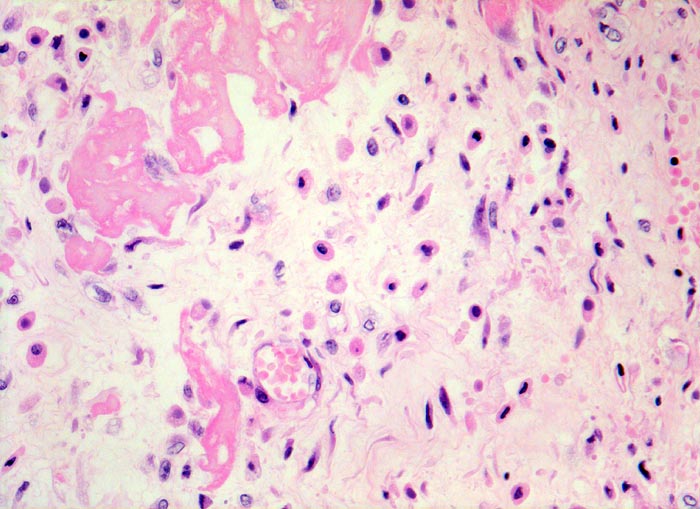

PathoPic ID 4533 - fibrinöse Perikarditis

fibrinöse Perikarditis

Entzündung / Reparatur

Perikard

Körperhöhlen, Serosa

Lockeres ödematöses Granulationsgewebe mit

kapillären Gefässen,

Histiozyten (Gewebsmakrophagen) und

Fibroblasten organisieren die

Fibrinauflagerungen.

Patientin verstorben in Urämie.

320

87